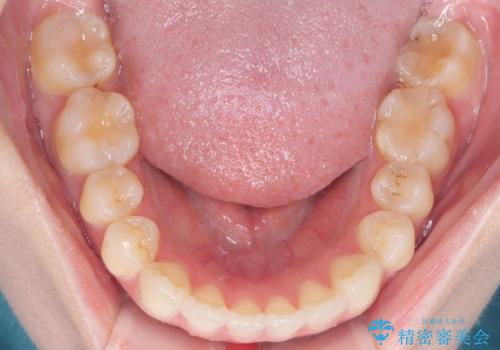

- 右上の八重歯と歯並びのデコボコを気にされて来院されました。精密な検査の結果、歯列のスペースがわずかに不足していることが判明。患者様の「抜歯を避けたい」というご希望を最大限に尊重し、アンカースクリュー(TAD)を用いて奥歯(臼歯部)全体を後方へ移動させることで、八重歯が並ぶスペースを確保する治療計画を立案しました。装置にはワイヤー矯正を使用し、確実で効率的な歯の移動を目指します。

今回のワイヤー矯正治療では、抜歯せずに歯を並べるスペースを作るため、特殊な小さなインプラントであるアンカースクリュー(TAD)を一時的に使用しました。このアンカースクリューを固定源として、奥歯(臼歯部)全体を後方へ遠心移動させました。従来の矯正では難しかったこの奥歯の移動を確実に行うことで、前歯の八重歯を適切な位置に並べるスペースを確保。治療の結果、抜歯することなく右上の八重歯と叢生が解消され、機能的にも審美的にも整った美しい歯並びを獲得していただけました。